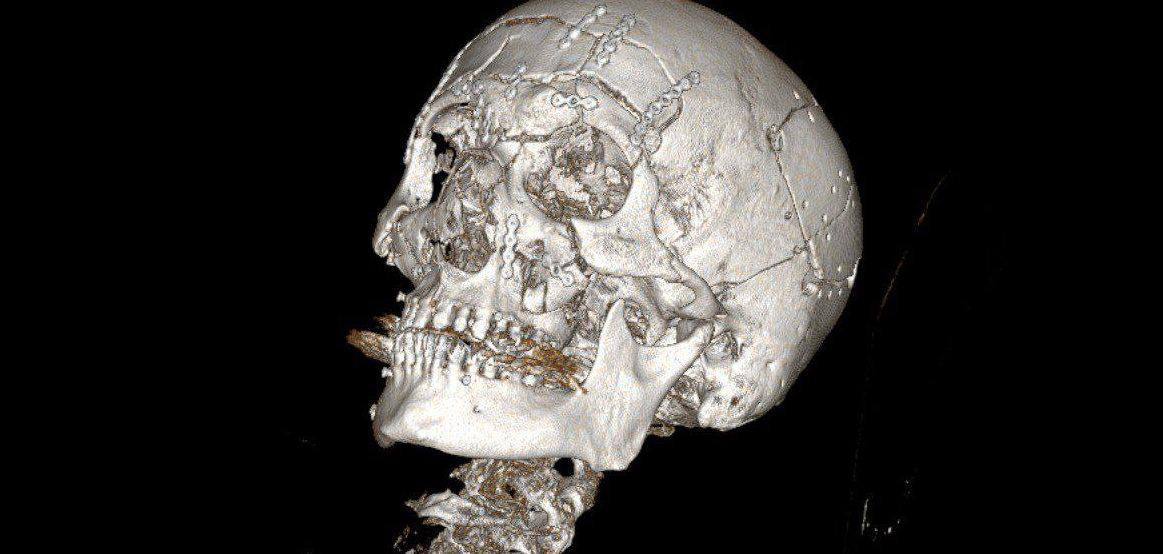

На нейрохирургическом этапе специалисты удалили костные отломки лобной кости, провели ревизию лобной пазухи и закрыли дефект твёрдой мозговой оболочки. Затем челюстно-лицевые хирурги вернули на место костные фрагменты и восстановили лобную кость, часть глазницы, контуры орбит, верхнюю челюсть и правую половину нижней челюсти, зафиксировав их титановыми минипластинами.